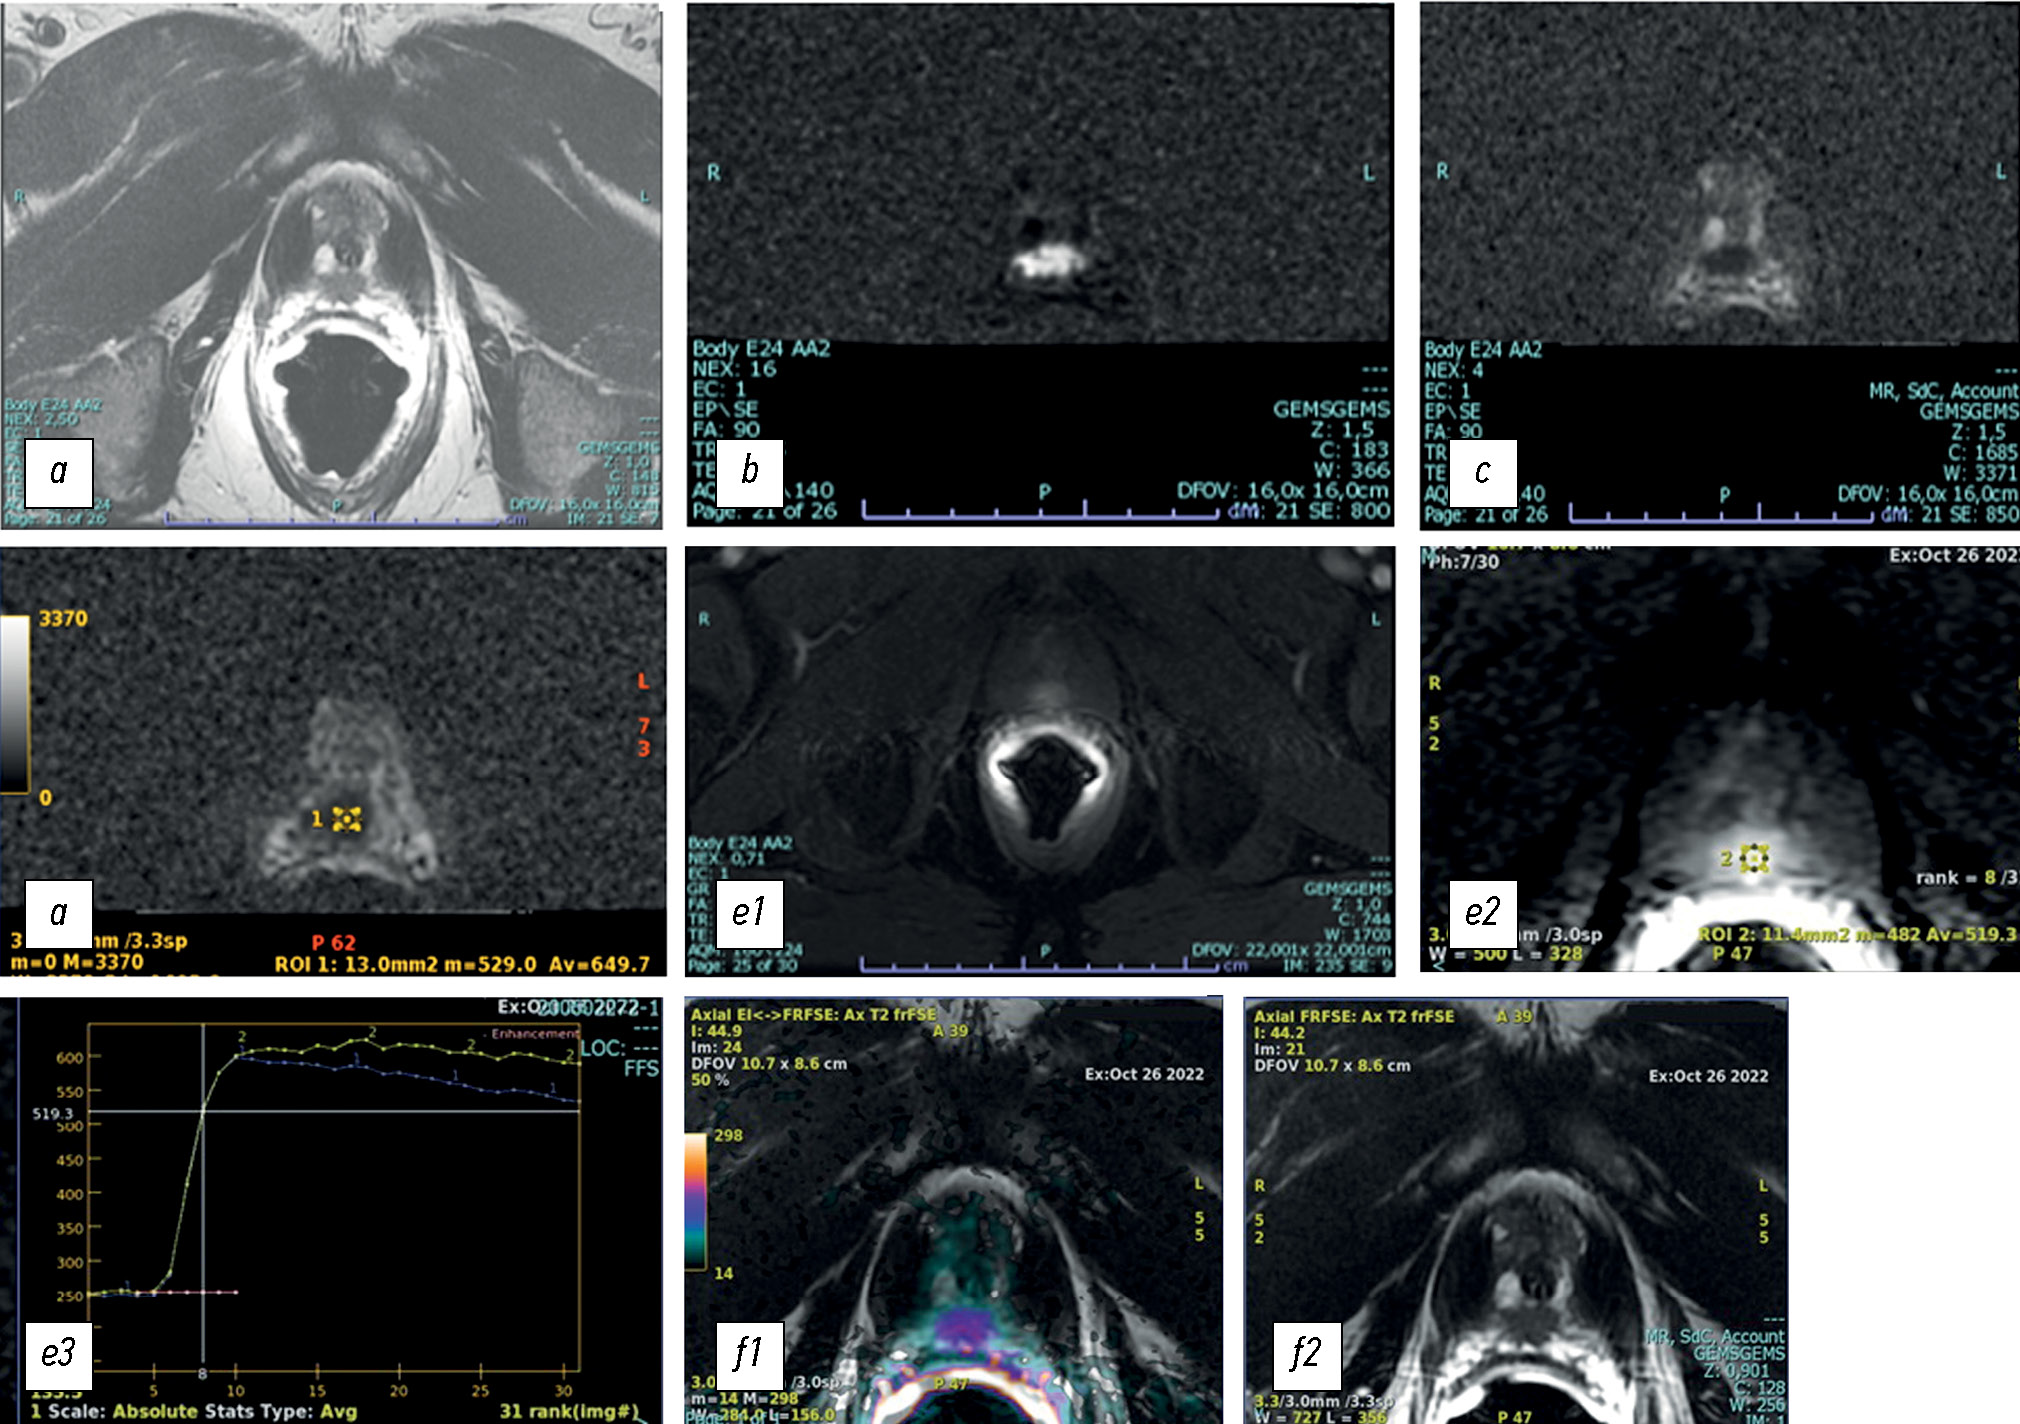

Optimization of left ventricular lead implantation based on combined myocardial perfusion scintigraphy and computed tomography data

Abstract

BACKGROUND: Successful cardiac resynchronization therapy in patients with chronic heart failure critically depends on the selection of the optimal implantation site for the left ventricular lead. A hybrid imaging approach combining cardiac venous computed tomography and myocardial perfusion scintigraphy may assist in identifying the target vein and improve procedural efficacy.

AIM: The work aimed to evaluate the feasibility of a multimodal imaging approach for optimizing left ventricular lead implantation in cardiac resynchronization therapy.

METHODS: It was a prospective, observational, single-center, non-randomized controlled study. Patients with chronic heart failure and indications for cardiac resynchronization therapy in accordance with current guidelines were enrolled. Prior to the procedure, the patients underwent computed tomography of the cardiac veins to visualize venous anatomy and myocardial perfusion scintigraphy to assess the extent of left ventricular perfusion impairment. The optimal site for left ventricular lead placement was identified using a three-dimensional reconstruction of the coronary sinus fused with myocardial perfusion scintigraphy data. To assess the effectiveness of the hybrid approach, a reference group was formed, in which cardiac resynchronization implantation was performed using the standard method, without preprocedural evaluation of coronary venous anatomy or myocardial scarring. Six months after cardiac resynchronization therapy, all patients underwent echocardiography to evaluate treatment effectiveness. Echocardiographic response was defined as a reduction in left ventricular end-systolic volume by ≥15% and/or an increase in ejection fraction by ≥5%.

RESULTS: The imaging group consisted of 40 patients with chronic heart failure, whereas the reference group included 30 patients with the same diagnosis. Six months after cardiac resynchronization therapy, a positive treatment response was observed in 33 patients (82%) in the imaging group, significantly higher than in the reference group (17 patients, 57%), p = 0.031. In the imaging group, the reduction in left ventricular end-systolic volume was statistically significant compared with the reference group and amounted to −52 [−71; −22.5] mL versus −21 [−64; −1] mL, respectively (p = 0.039). The increase in left ventricular ejection fraction was 7.5 [4.5; 15]% in the imaging group and 4.5 [0; 13]% in the reference group, with no statistically significant difference (p = 0.082).

CONCLUSION: The use of cardiovascular imaging methods, including cardiac venous computed tomography and myocardial perfusion scintigraphy, was associated with an increased proportion of responders to cardiac resynchronization therapy.